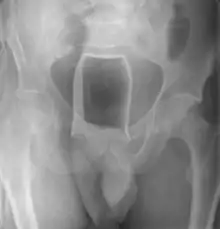

Стеклянная бутылка в просвете прямой кишки на рентгенограмме | |

Обычно делают несколько рентгеновских снимков, чтобы точно определить место нахождения инородного тела. Инородные тела из малоконтрастного материала (например, пластика) могут потребовать ультразвукового исследования или компьютерной томографии.[28] Магнитно-резонансная томография противопоказана, особенно если неизвестен материал инородного тела. Инородные тела прямой кишки могут проникать глубоко в толстую кишку, при определенных обстоятельствах вплоть до правого изгиба ободочной кишки.[9]